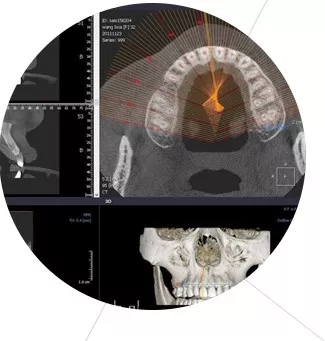

北京美萊口腔科微創(chuàng)牙齒矯正采用口腔CT及3D導(dǎo)板技術(shù),有效植入種植體,實(shí)現(xiàn)了即拔即種、創(chuàng)口微小、不翻瓣、一次成型、術(shù)后即可飲食的種植效果,使用年限超40年。

采用國(guó)際口腔CBCT技術(shù)診斷,從任意角度立體化觀察牙槽骨情況,確定較佳種植位置,舒適度高愈合快。